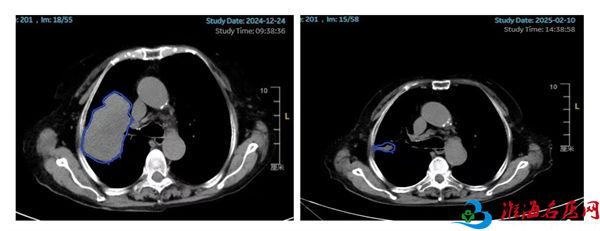

80岁的患者李女士(化名)2024年2月确诊为右肺腺鳞癌,经过靶向治疗、化疗后出现多次进展。2024年12月24日查胸部CT提示右肺上叶病灶增大至95mm×64mm(图1左侧所示)。考虑肿瘤体积巨大,肿瘤内部可能出现坏死、乏氧,常规放疗难以取得理想的治疗效果,并且大概率会对肿瘤周围的心脏、肺、臂丛神经等正常组织造成较大损伤,严重影响患者的生活质量,肿瘤放疗科副主任丁昕组织蒋爱军主任医师、李亮副主任物理师等团队成员进行综合评估和细致讨论,决定采用空间分割放疗技术。李女士整个疗程接受了6次放疗(常规放疗一般至少需要30次),住院时间明显缩短。治疗结束后李女士自觉咳嗽症状明显好转,1月后,2025年2月10日复查胸部CT提示右肺上叶的巨大肿瘤几乎完全消失(图1右侧所示),取得了出乎意料的治疗效果。

图1.患者治疗前后的影像对比(蓝色标记的为肿瘤部位)